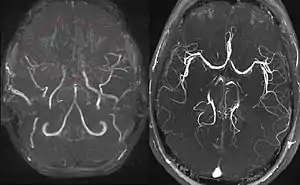

Left: MIP reconstructed MR angiography of a 11-year-old girl with moyamoya disease.

Right: healthy patient, for comparison.

Magnetic resonance angiography (MRA) is also useful in diagnosing the disease with good correlation with Suzuki's grading system.[15]